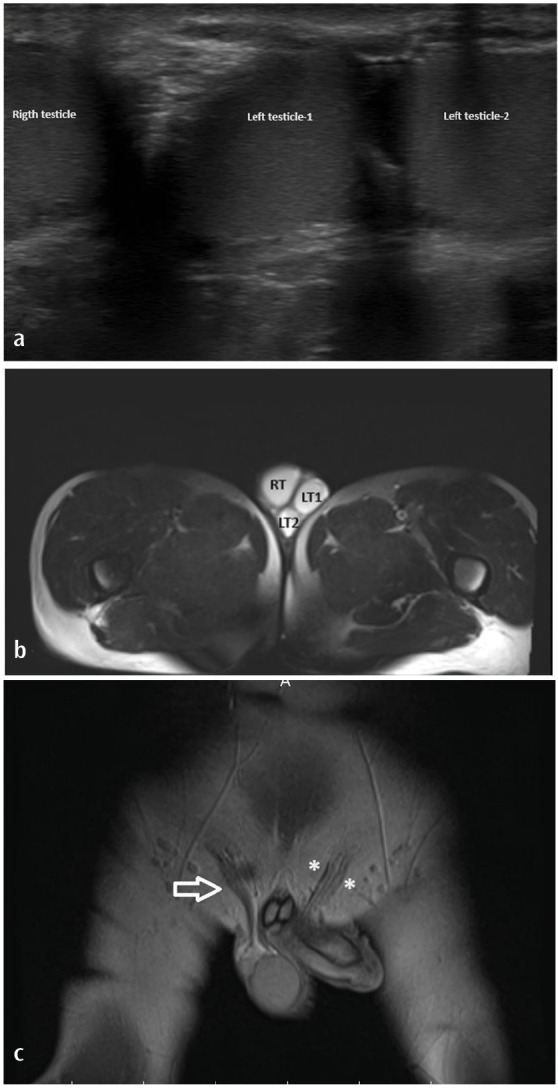

Supernumerary Testis (Polyorchidism)

多余睾丸(多精症)。